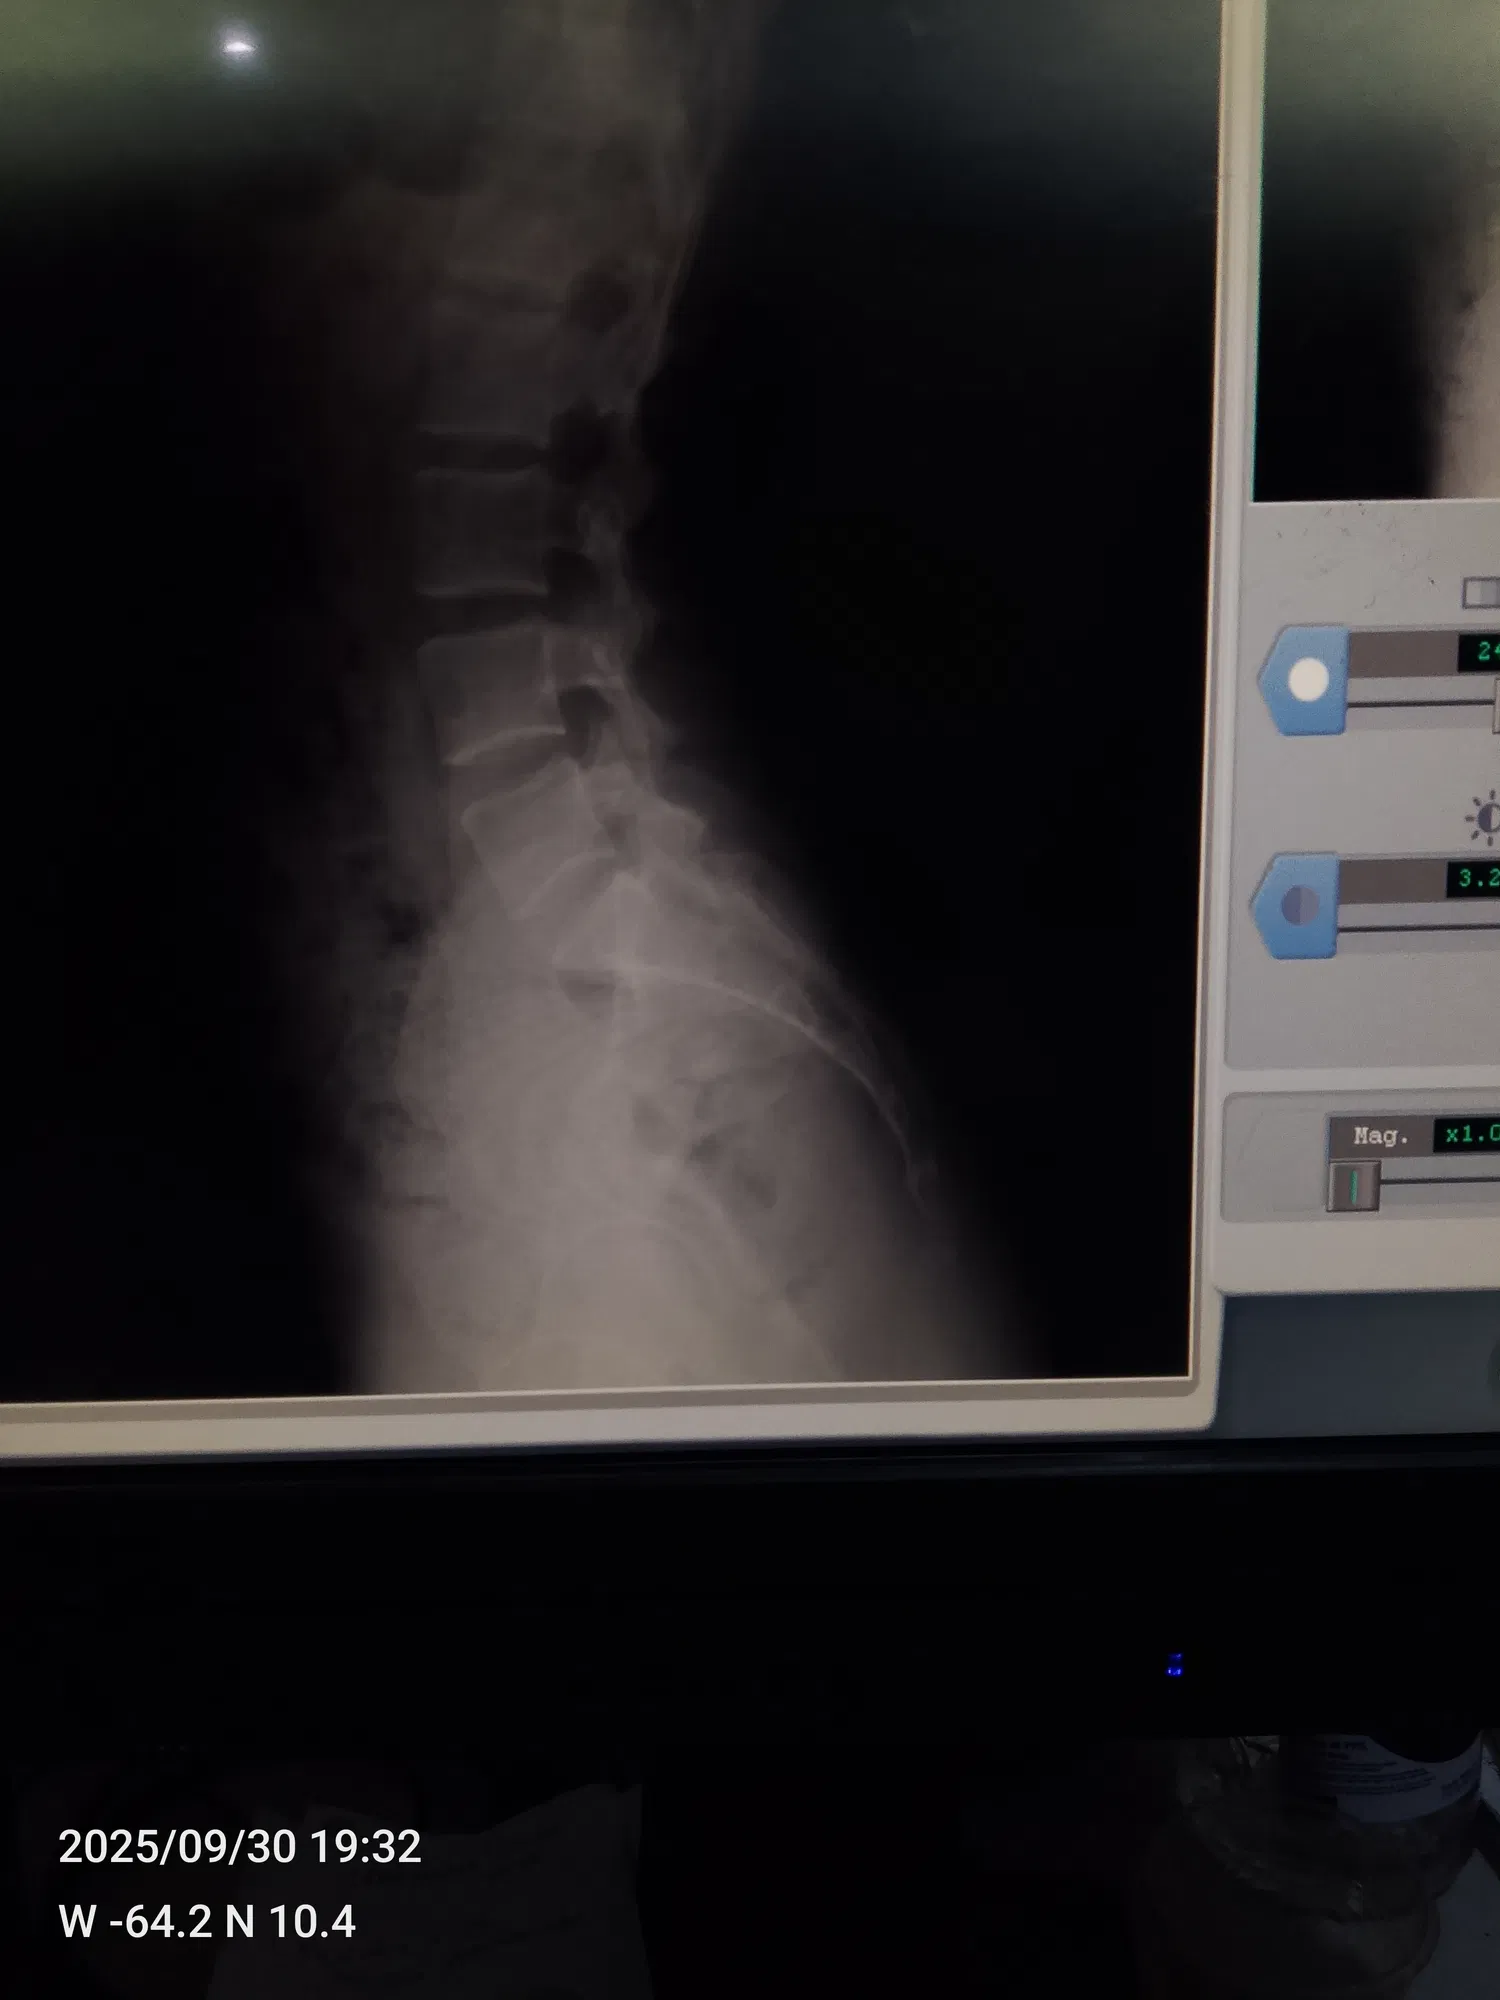

<liketuimages> <center>         </center> </liketuimages> ### Holaaa queridos amigos,¿cómo han estado? espero que hayan tenido un excelente fin de semana ❤️✨ he estado un poco perdida de por acá ya que me he estado sintiendo demasiado mal 😣 hace días les comenté que fui al traumatólogo ya que me había caido en dónde trabajo y me di un golpe súper fuerte en la columna ☹️ >Hello dear friends, how have you been? I hope you had a great weekend ❤️✨ I've been a little absent from here because I've been feeling really bad 😣 A few days ago, I told you that I went to the orthopedist because I fell at work and hit my spine really hard ☹️ ---- ### Desde que me caí no aguanto los dolores en la columna, coxis y cervical, del mismo golpe que me di tuve un derrame ( parecía el periodo pero eso no era ya que yo ya había visto periodo ese mes) mi mamá me llevo a el traumatólogo y la doctora me mando un tratamiento y reposo por una semana,en las placas que me hice antes de ir no salía nada malo.. >Since I fell, I can't stand the pain in my spine, tailbone, and neck. From the same blow, I had a hemorrhage (it looked like my period, but it wasn't because I had already had my period that month). My mom took me to the orthopedist, and the doctor prescribed treatment and rest for a week. The X-rays I had taken before going didn't show anything wrong. --- ### Cumplí mi reposo y me tomé el tratamiento que me mandó la doctora pero la verdad eso no me hizo efecto me sentía muy mal, las pastillas me calmaban el dolor un poco ya después el dolor volvió más fuerte ☹️ fui y me hice otras placas más y el radiólogo nos dijo que estaba teniendo una pequeña desviación y que se veía como una fisura que fuera a el traumatólogo a ver que era, mi mamá me llevo nuevamente para que la doctora y la misma dijo que no tenía nada y me mandó a tomar pregabalina y la verdad amigos me tomé una sola pastilla y me dió taquicardia sentía que me iba a morir me dió mucho miedo y no me la tomé más, mi mamá tuvo que buscarme la cita con otro traumatólogo, así que el día martes el doctor Luis Cova me va a ver.. >I rested and took the treatment prescribed by the doctor, but honestly, it didn't work. I felt terrible. The pills calmed the pain a little, but then the pain came back even stronger. ☹️ I went and had more X-rays taken, and the radiologist told us that I had a slight deviation and that it looked like a crack. He said I should go to the orthopedist to see what it was. My mom took me back to the doctor, and she said there was nothing wrong and prescribed pregabalin. To be honest, friends, I took just one pill and it gave me tachycardia. I felt like I was going to die. I was really scared and didn't take any more. My mom had to make an appointment with another orthopedist, so on Tuesday, Dr. Luis Cova is going to see me. --- ### Muchas personas ya nos han dicho que si tengo una desviación y algo más que obviamente lo va a ver el doctor, así que bueno esperaré hasta el martes Pero les digo amigos, ese dolor me hace llorar es demasiado fuerte 😭☹️ por eso he estado perdida de por acá,ya pronto volveré con mucho contenido para ustedes ❤️ síganme en mis redes de tiktok e Instagram por allá siempre subo algo ❤️ mi usuario de tiktok es @Fiorem17 y de Instagram es @Fiorem19 >Many people have already told us that if I have a deviation and something else that the doctor will obviously see, then I'll wait until Tuesday. But I tell you, friends, that pain makes me cry, it's too strong 😭☹️. That's why I've been missing from here. I'll be back soon with lots of content for you ❤️ Follow me on TikTok and Instagram, I always post something there ❤️ My TikTok username is @Fiorem17 and my Instagram is @Fiorem19 --- ### Acá les dejare algunas fotos que me he tomado jajaja y les quiero mostrar una torta que hice hoy en la mañana con ayuda de mi hermano ajajaja la hice en mi cuarto sentada en la cama así que fue un rato hacerla jajajaja y quedó linda, les dejare también las fotos de las placas por si algunos de ustedes es doctor las vea y me dice si ve algo malo por fa ☹️☹️☹️ >Here are some photos I took, hahaha, and I want to show you a cake I made this morning with my brother's help, hahaha. I made it in my room sitting on my bed, so it took a while, hahaha, but it turned out cute. I'll also leave you the photos of the X-rays in case any of you are doctors and can take a look and tell me if you see anything wrong, please ☹️☹️☹️ --- ##### <div class="pull-left"> - ### El texto es completamente de mi autoría. </div> ##### <div class="pull-right"> - ### The text is entirely by me. </div> --- ##### <div class="pull-left"> - ### Traducción realizada con DeepL Traslate. </div> ##### <div class="pull-right"> - ### Translation using DeepL Traslate. </div> --- For the best experience view this post on [Liketu](https://liketu.com/@fiorem17/un-nuevo-post-para-ustedes)